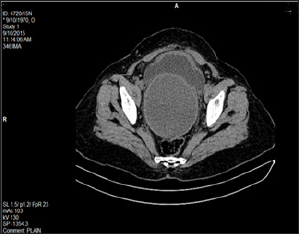

The mass appeared to be arising from anterior vaginal wall. A provisional diagnosis of anterior vaginal wall cyst was made and imaging studies performed. The ultrasound was suggestive of retention cyst (Figure 2). CT scan too pointed towards retention vaginal cyst (Figure 3). Since the diagnosis was not clear; the case was taken up for detailed examination under anesthesia, the mass was occupying the whole of vagina hence one could not go beyond the mass to locate the cervix, detailed per speculum examination under anesthesia revealed a small discolored spot (Figure 4) which when probed exuded tarry material (Figure 5). A diagnosis of cervical stenosis with retained blood was made and cervical opening was dilated to allow the collected blood to drain out. Appx 700 ml (Figure 6) of dark chocolate material was removed and cervix attained almost normal appearance and now the uterus could be palpated distinctly which appeared of normal size and shape. The lump abdomen had disappeared.

Figure 2: USG suggestive of retention cyst.

Figure 3: CT scan showing retention vaginal cyst.